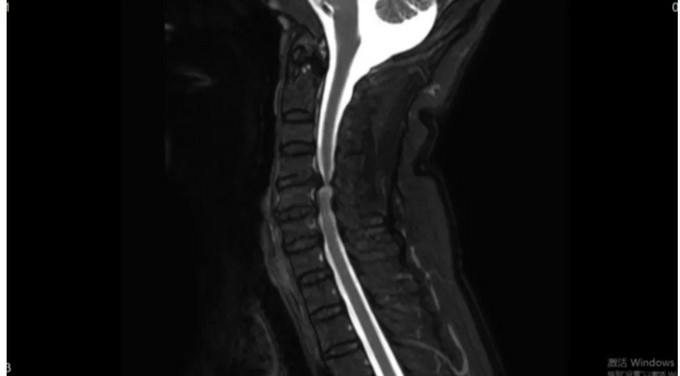

術前影像

頸椎CT矢狀位

頸椎MRI矢狀位,可以看到患者的頸神經(jīng)被明顯壓迫